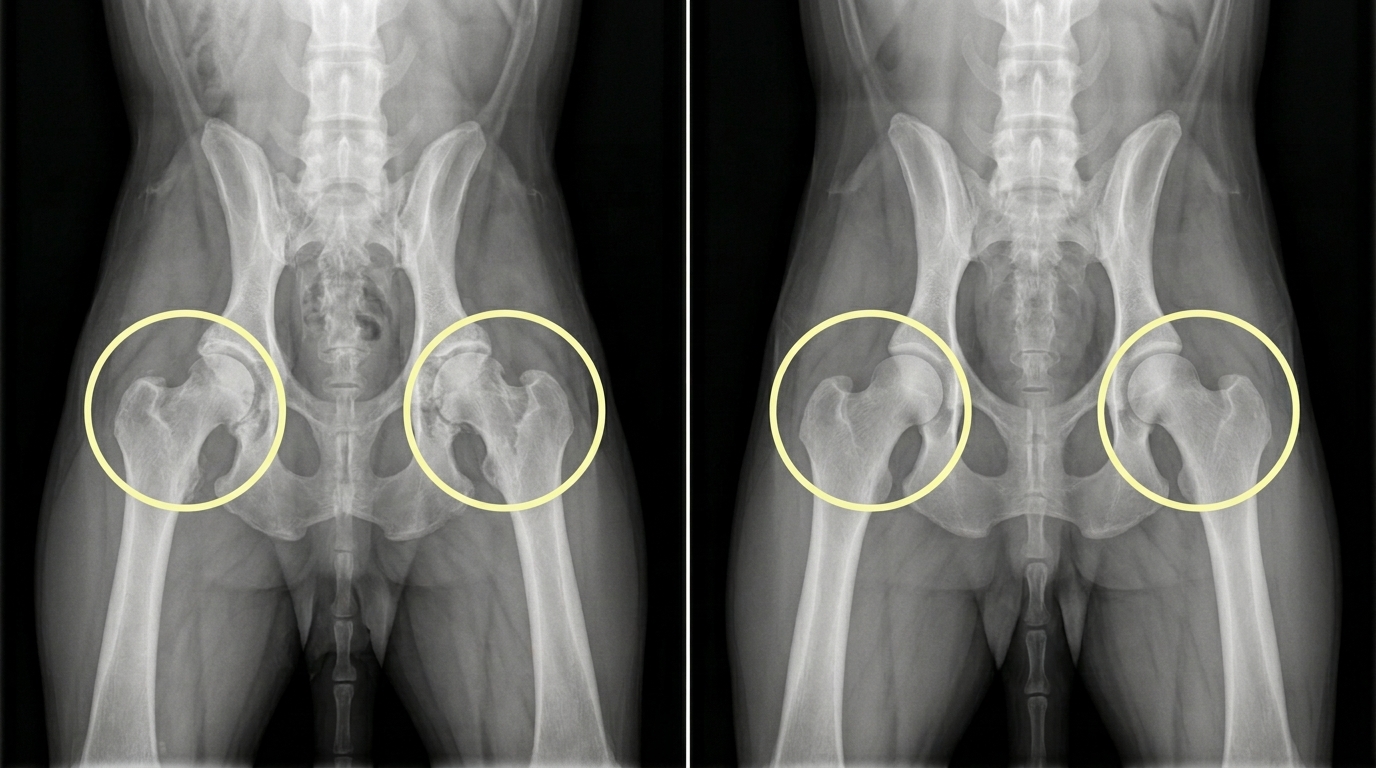

현재에는 과학의 발전과 함께 과거의 문제점을 바로잡기 위한 연구자와 관계자들의 부단한 노력이 이어지고 있습니다. 안내견으로 잘 알려진 래브라도 리트리버 품종도 앞선 불독과 같이 지속적인 근친교배로 인해 고관절 형성에 이상이 발생하여 통증과 움직임을 제한하는 고관절 이형성증으로 크게 고통받아왔습니다. 하지만 최근 국립 충남대학교 김민규 교수팀에서 고관절 이형성증을 유발하는 유전자 돌연변이를 교정한 래브라도 리트리버 복제 개를 생성에 성공하여 래브라도 품종에 씌어있는 "저주"의 연결고리를 끊어낼 수 있는 새로운 방향을 제시하였습니다. 우리나라의 대표적인 육우인 한우에서도 전국 200만 마리에 달하는 한우의 아버지 격인 종모우를 대상으로 지속적인 DNA 검사를 통해 유전병 보인자 유무를 선별하여 유전병의 발생을 최소화하고 있으며 교배 계획을 수립할 때 유전적인 유사도를 고려하여 근친교배를 지양하는 노력을 더 하고 있습니다. 호주 시드니대학교에서 운영하는 OMIA(Online Mendelian Inheritance in Animals)는 약 520여 종의 동물에서 확인되는 유전형질과 변이 및 유전병을 데이터베이스화하여 지속적으로 업데이트를 통해 유전병 연구에 이바지하고 있습니다.

래브라도의 고관절 (좌측)고관절 이형성증을 보이는 일반 래브라도의 고관절, (우측)정상적인 고관절을 보여주는 복제 래브라도 (출처: scientific reports)